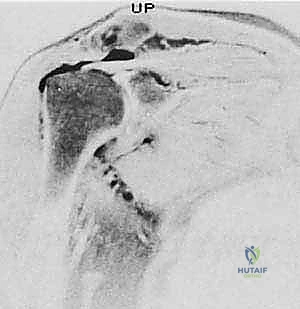

- الرنين المغناطيسي (MRI): هو المعيار الذهبي. يوضح الرنين المغناطيسي حجم التمزق، موقعه، مدى تراجع (انسحاب) الوتر، وما إذا كان هناك ضمور دهني في العضلة.

- الأشعة السينية (X-rays): لاستبعاد وجود كسور، وتقييم المسافة تحت الأخرم، ورؤية النتوءات العظمية أو التكلسات التي قد تكون سبباً في قطع الوتر.